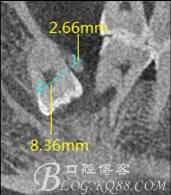

二、術(shù)前CBCT影像:

圖6.測(cè)量48頰、舌側(cè)骨板厚度。

圖7.測(cè)量牙冠近遠(yuǎn)中徑的大小及遠(yuǎn)中骨板的厚度